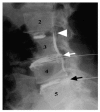

Discogenic lower back pain (DLBP) is the most common type of chronic lower back pain (LBP), accounting for 39% of cases, compared to 30% of cases due to disc herniation, and even lower prevalence rates for other causes, such as zygapophysial joint pain. Only a small proportion (approximately 20%) of LBP cases can be attributed with reasonable certainty to a pathologic or anatomical entity. Thus, diagnosing the cause of LBP represents the biggest challenge for doctors in this field. In this review, we summarize the process of obtaining a clinical diagnosis of DLBP and discuss the potential for serum-based diagnosis in the near future. The use of serum biomarkers to diagnose DLBP is likely to increase the ease of diagnosis as well as produce more accurate and reproducible results.